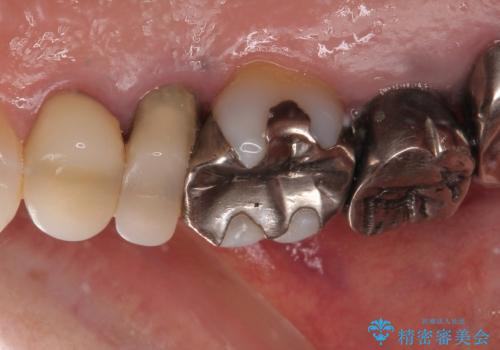

- むし歯の放置期間が長く、クラウンの幅が狭くなってしまった歯を気にして来院された患者様です。

細長いクラウンの周りが汚れてきたこと、奥の銀歯が笑ったときに見えることから、3本をセラミッククラウンにて補綴し、大きさのバランスを整えることとしました。